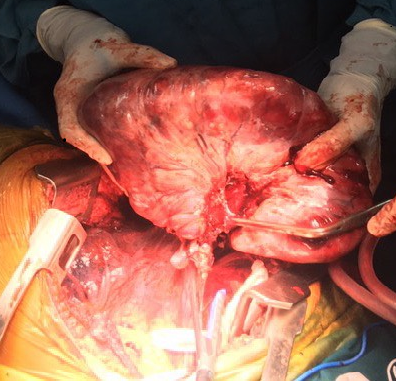

Các bác sĩ chẩn đoán bệnh nhân T.T.L bị u trung thất lớn chèn ép tim, phổi và có chỉ định phẫu thuật khẩn mở ngực trái qua khoang liên sườn VI trái để bóc tách khối u chiếm gần trọn khoang màng phổi trái, nặng hơn 3kg, bề mặt trơn láng, tăng sinh mạch máu, dính vào tim, phổi, cơ hoành.

Sau gần 3h phẫu thuật các bác sĩ đã cắt được khối u ra khỏi bệnh nhân mà không có biến chứng gì. Dự kiến Bệnh nhân sẽ được rút dẫn lưu sau 4 ngày, hậu phẫu ổn định ra viện sau 9 ngày.